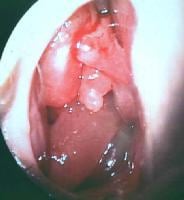

The production of this allergic mucin and its eventual clinical, histologic, and radiographic characteristics are unique to allergic fungal sinusitis (AFS) and serve as a hallmark of the disease. Grossly, allergic fungal mucin is thick, tenacious, and highly viscous. Its color may vary from light tan to brown or dark green, as depicted in the images below. Its characteristic gross appearance has resulted in the use of such descriptive terms as peanut butter and axle grease when referring to allergic fungal mucin.

Left middle meatus with suctioning of thick allergLeft middle meatus with suctioning of thick allergic mucin from the ethmoid bulla in the center of the picture; the end of the suction is in the inferior portion of the picture.The viscosity of a thick allergic mucin being suctThe viscosity of a thick allergic mucin being suctioned from the nasal cavity and vestibule in a patient with allergic fungal sinusitis.